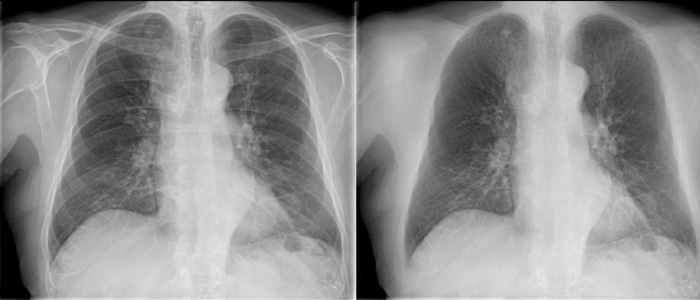

Bone Suppression**

Innovative image enhancement technology designed to increase the clarity of adult erect chest radiographs by suppressing bones on digital images.

• More confident image interpretation

• Enables detection of 1 in 6 nodules previously missed

• Fully integrated into the Eleva workflow

• Images automatically added to patient files